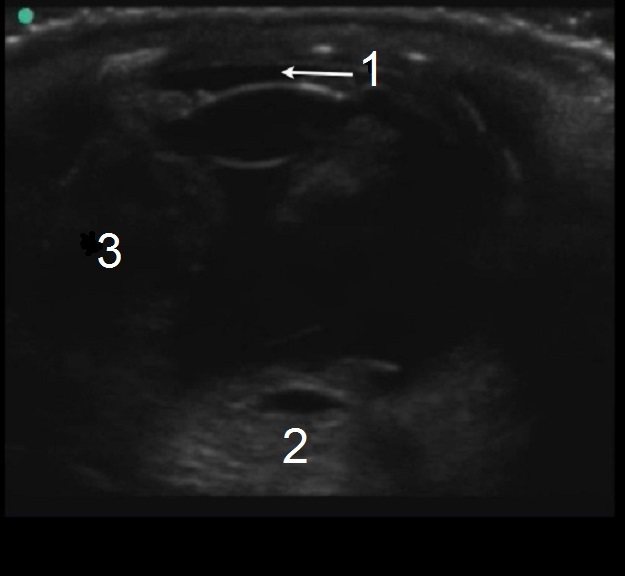

Ocular Ruptured Globe Image

Flat Anterior Chamber

Loss of Spherical Shape

Vitreous Hemorrhage